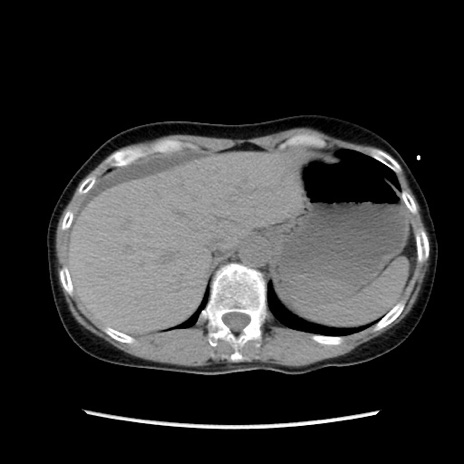

症例32(横断像)

【症例】40歳代 女性

【主訴】上腹部痛、嘔気・嘔吐

【現病歴】約9時間前頃から急に上腹部痛、嘔気、嘔吐が出現。改善しないため救急要請。

【既往歴】子宮頚癌(広汎子宮全摘術、放射線療法)、腸閉塞

【身体所見】腹部:平坦、軟、腸雑音亢進、上腹部を中心に腹部全体に圧痛あり。

【データ】WBC 8400、CRP 0.03